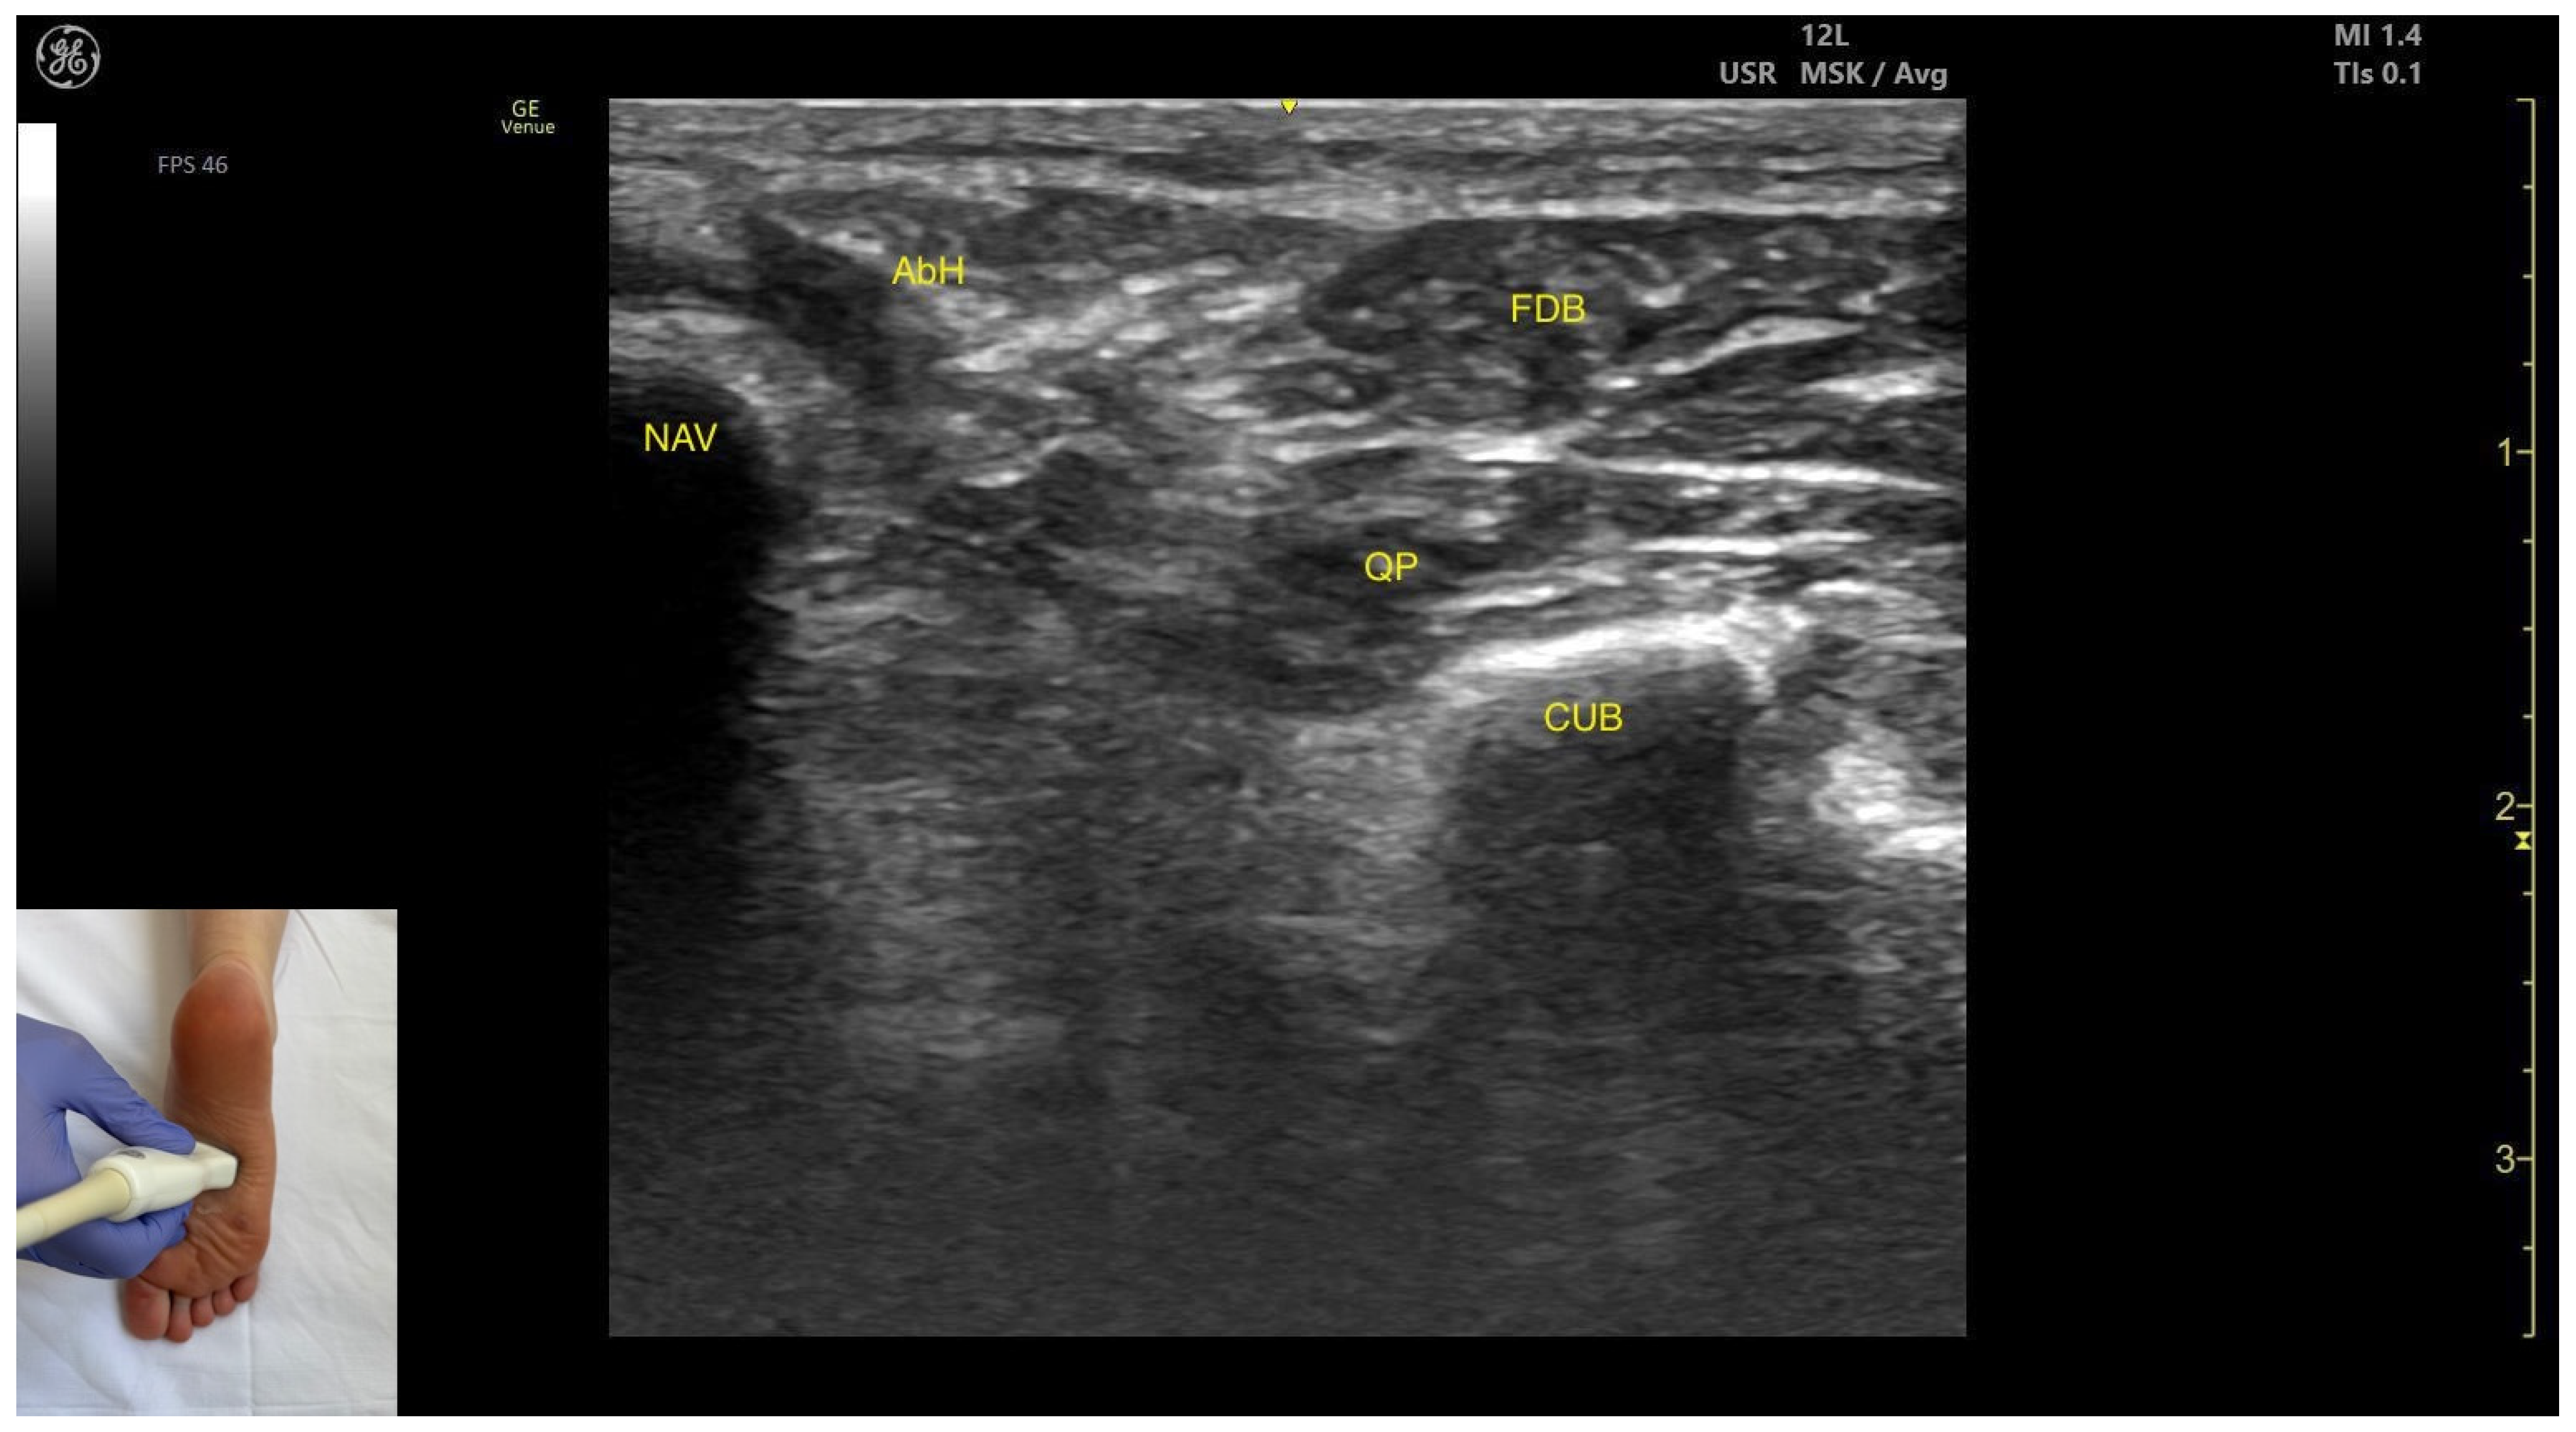

3.8.2. Ultrasound Identification

3.8.3. Key Ultrasound Landmarks

- Muscle position: It is a superficial plantar muscle layer. The quadratus plantae is located deep to the FDB. Medial to the FDB and quadratus plantae the abductor hallucis (AbH) is identified.

- External fascia: It features a prominent fascia separating it from the subcutaneous tissue, plantar aponeurosis and from the quadratus plantae, which is important during BoNT-A injection.

- Dynamic evaluation: During dynamic evaluation, scanning toward the calcaneous, a reduction in muscle thickness of the flexor digitorum brevis is observed. Muscle contraction is visible during flexion of toes II–V at the proximal interphalangeal joints (Video S4).

| Flexor Digitorum Brevis | Mid-plantar aspect of the foot | Plantar aponeurosis (superficial); abductor hallucis (medial); quadratus plantae (deep) | Transverse scan at mid-plantar aspect of the foot | Visualize flexor digitorum brevis as most superficial muscle and confirm muscle position and relations |